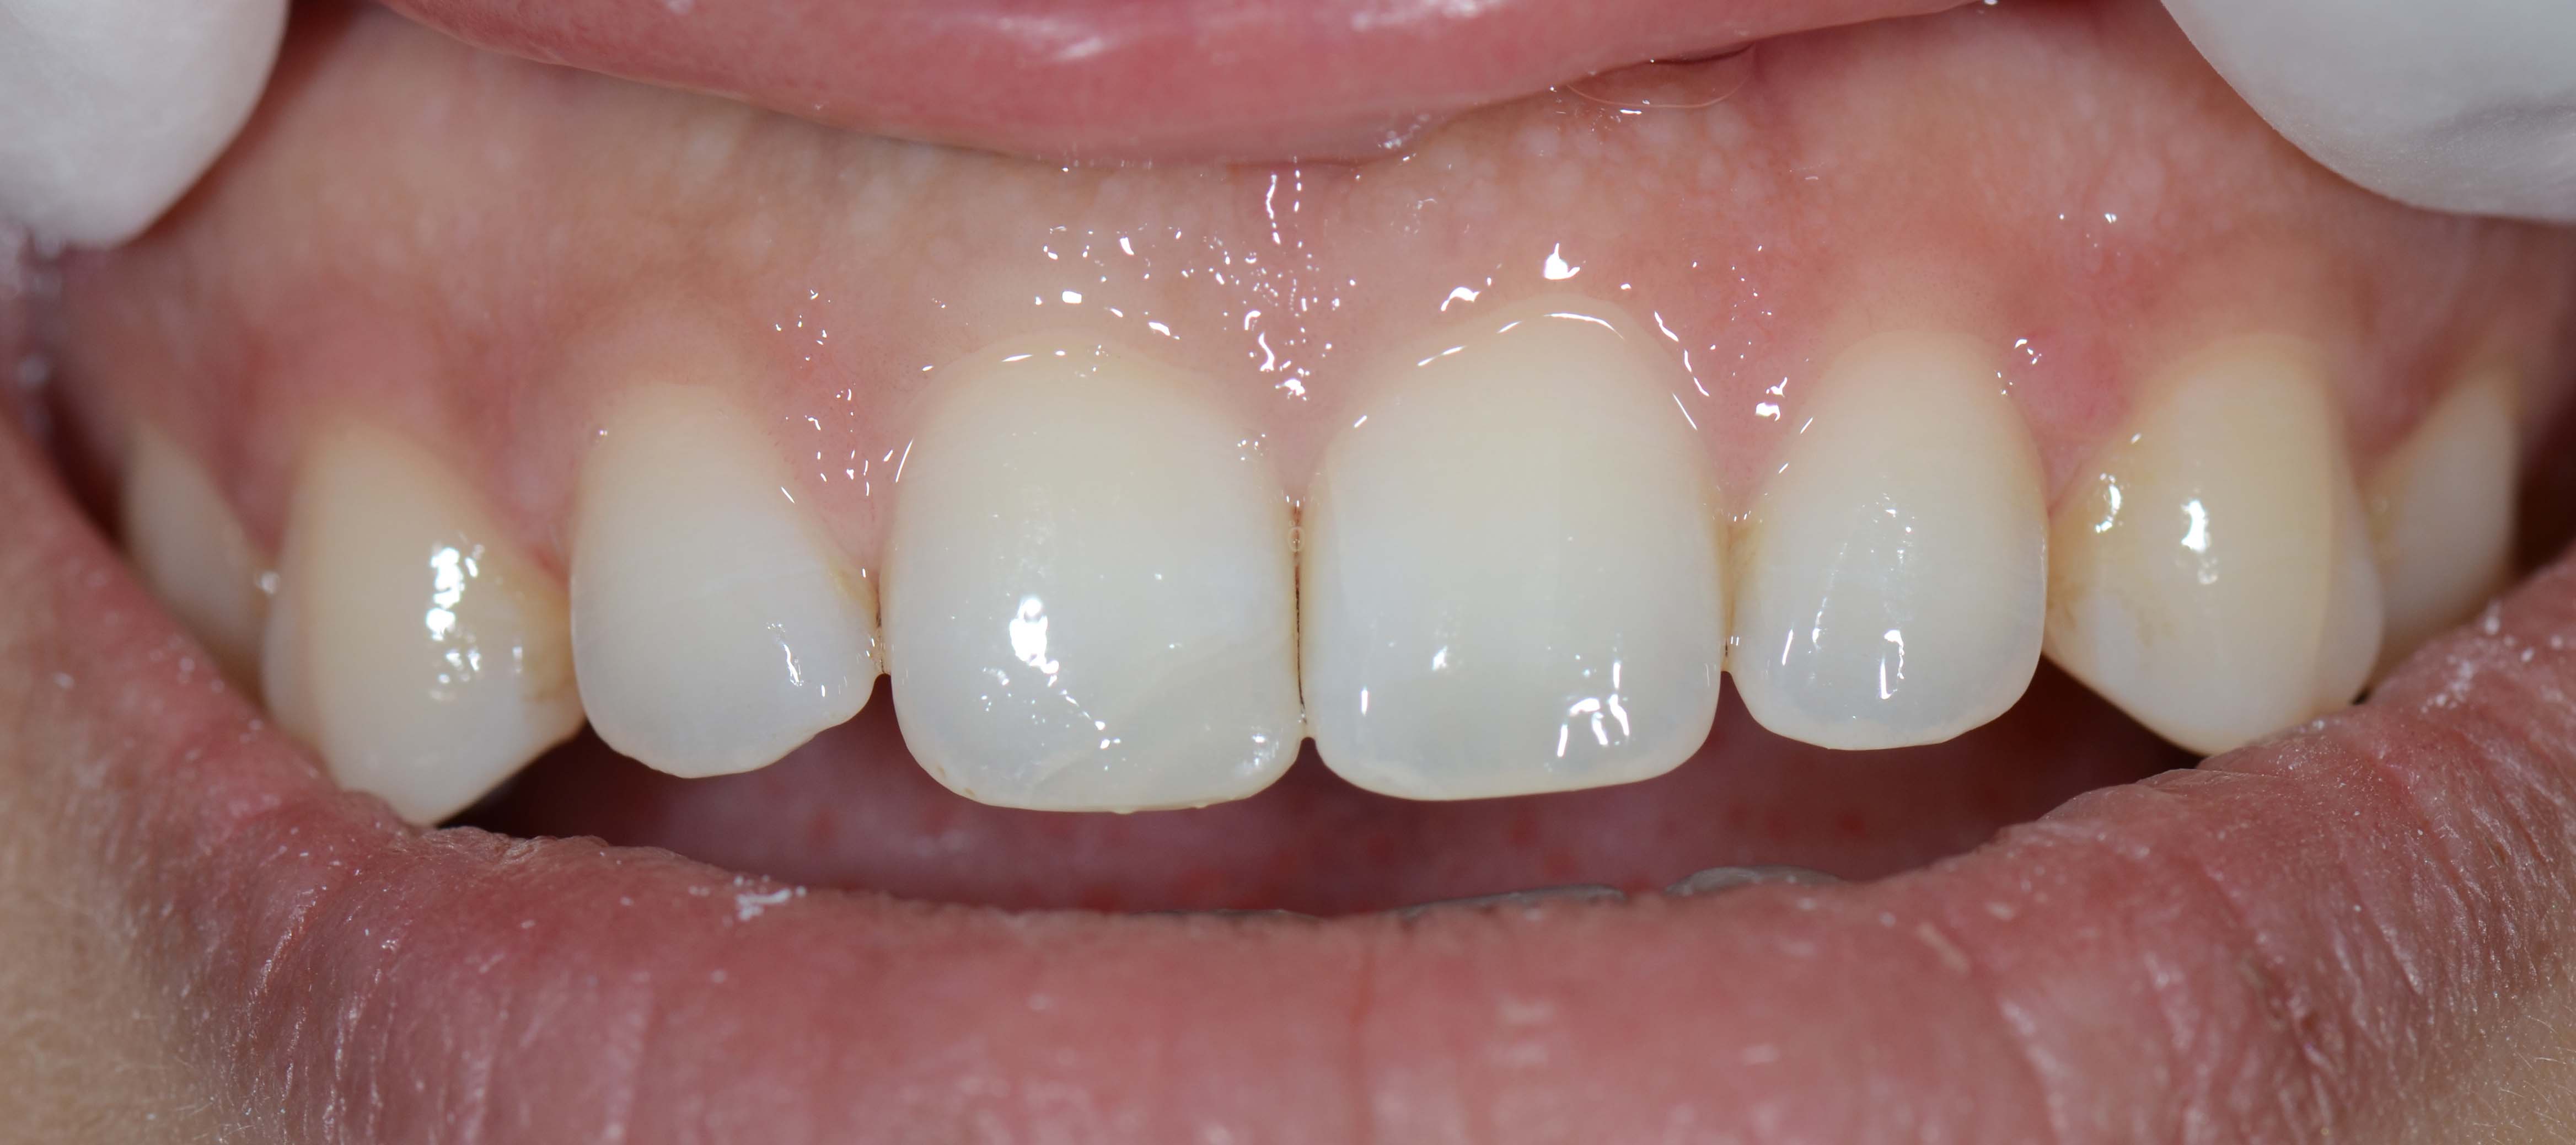

3. Fotografias

Após toda a informação recolhida serão apresentadas e discutidas as melhores opções de tratamento com o paciente.

Depois será fornecido um plano de tratamento com um orçamento para a sua execução.